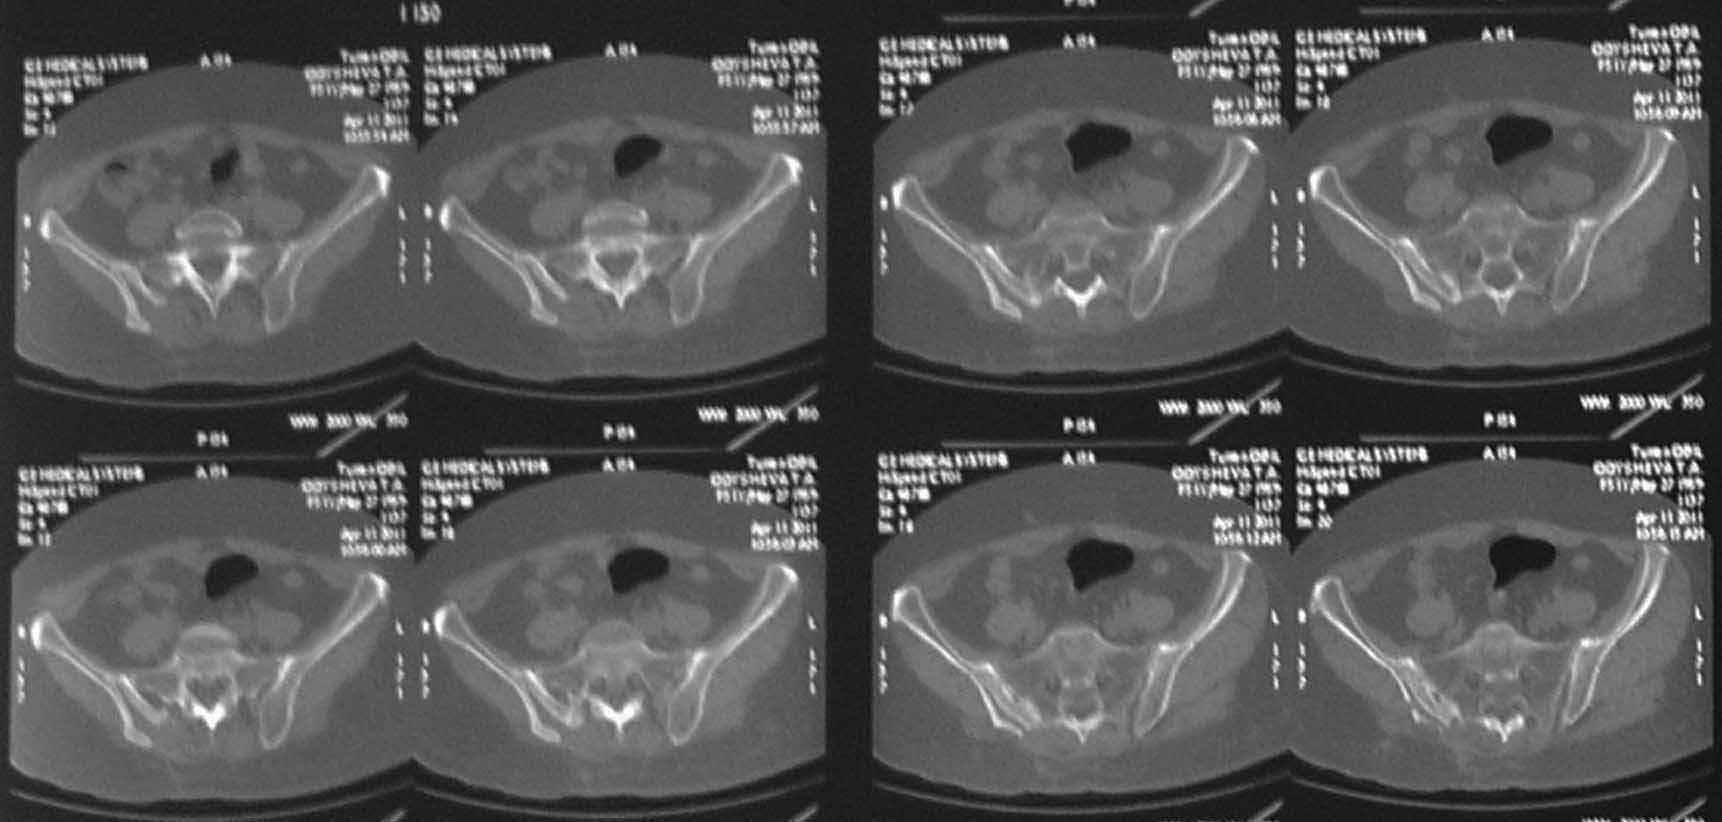

операции положительного эффекта не получено. На контрольной КТ от 04.2011 обнаружено что,

желаемого результата операции не получено(интересующий участок удален частично), при

этом имеется расслоение заднего отдела правой подвздошной кости. Сейчас клиника таже

самая, признаков воспаления внешне нет, по анализам тоже нет, туберкулеза нет и бруцеллеза

тоже нет.